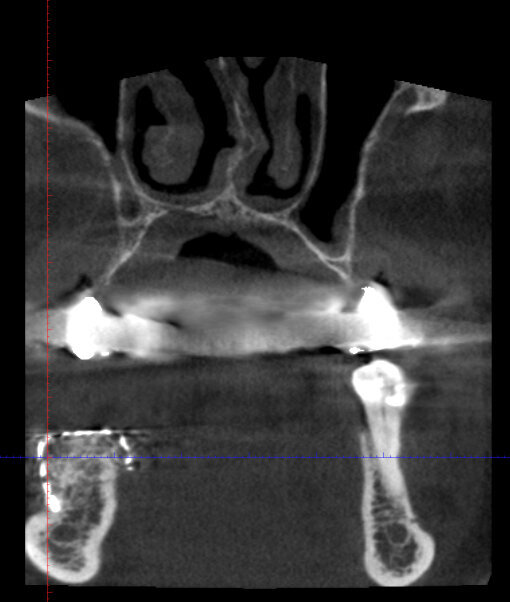

Figg. 1a-1c_Foto clinica e sezioni di CBCT iniziali in cui si evidenzia l’edentulia distale a elemento 4.3 con atrofia orizzontale estremamente accentuata e lieve atrofia verticale.